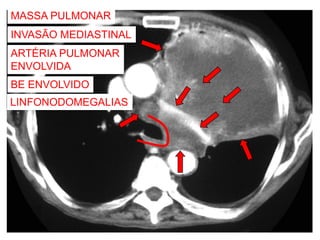

MASSA PULMONAR

ESQUERDA

NEOPLASIA PULMONAR

EXTENSÃO PARA O

MEDIASTINO?

TC = ESTADIAMENTO

TOMOGRAFIA COMPUTADORIZADA

INVASÃO MEDIASTINAL

ARTÉRIA PULMONAR

ENVOLVIDA

BE ENVOLVIDO

LINFONODOMEGALIAS